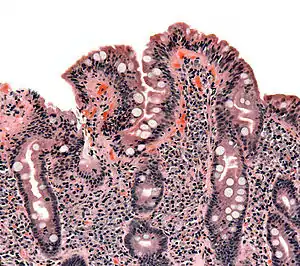

À la phase active de la maladie, avant le diagnostic et donc l'instauration d'un régime excluant le gluten, la majorité des malades ont une atrophie totale ou subtotale des villosités (disparition de ces dernières) au niveau de la paroi intestinale avec une nette augmentation du nombre de lymphocytes dans l'épithélium de cette dernière.

Cette atrophie est prédominante au niveau de l'intestin grêle proximal mais peut, quand l'atteinte est importante, être visible sur l'ensemble de l'intestin grêle. Elle conduit alors à un syndrome de malabsorption plus ou moins total avec notamment une malabsorption de la vitamine B12 au niveau du grêle distal. Le taux sanguin de cette dernière est alors très abaissé, provoquant une macrocytose.

Elle met en évidence une atrophie villositaire associée à une augmentation des lymphocytes intraépithéliaux, une hypertrophie des cryptes et une infiltration plasmolymphocytaire du chorion. Ces lésions sont évaluées selon la classification de Marsh, allant de I (simple augmentation isolée des lymphocytes intraépithéliaux) à IIIc (atrophie villositaire sévère)[53].